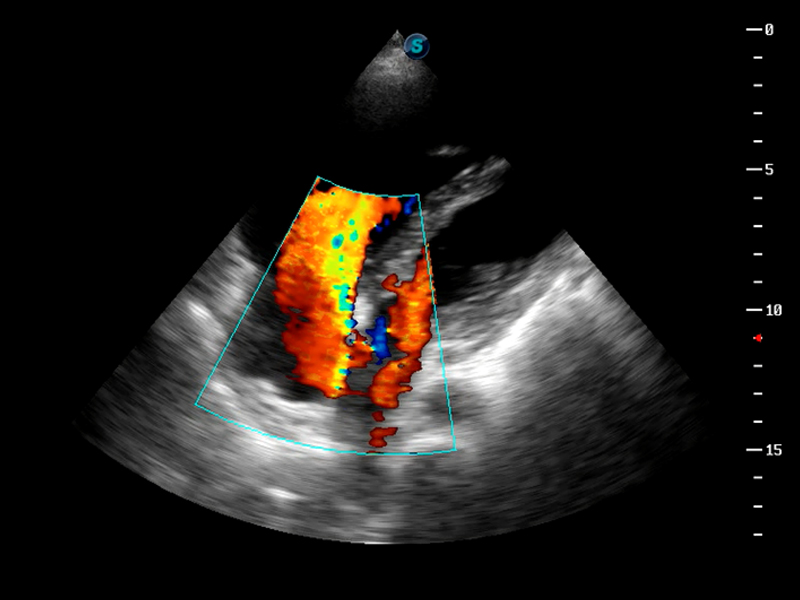

μ-Scan微米成像

脉冲反相谐波成像

TDI组织多普勒成像

AutoC智能血流追踪